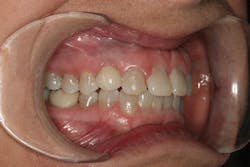

A 32-year-old white female presented for a cosmetic consultation. The patient reported that during her teenage years she had received orthodontic treatment to move her permanent maxillary canines mesially into the spaces that should have been occupied by her congenitally missing lateral incisors. She stated that her dentist, orthodontist, and oral surgeon had decided to place endosseous implants in the canine spaces due to the greater availability of bone in comparison to the bone available in the lateral positions (figure 1). As she grew older, she had become increasingly dissatisfied with the appearance of her smile and was seeking a more updated and esthetic solution (figure 2).

Figure 1